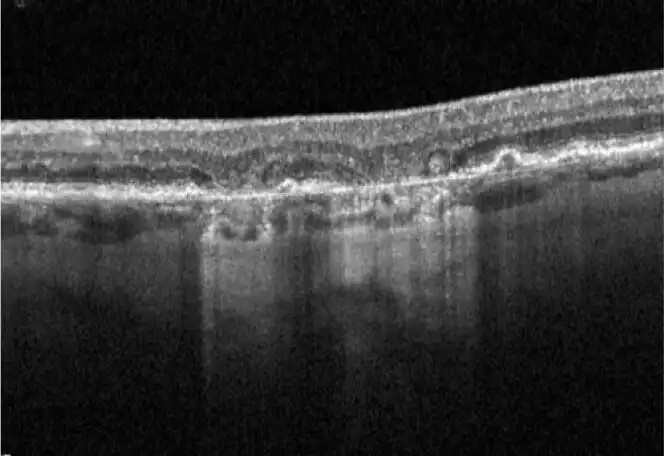

Neovascular AMD

- In clinical trials, use of IZERVAY was associated with increased rates of neovascular (wet) AMD or choroidal neovascularization (7% when administered monthly and 4% in the sham group) by Month 12. Over 24 months, the rate of neovascular (wet) AMD or choroidal neovascularization in the GATHER2 trial was 12% in the IZERVAY group and 9% in the sham group. Patients receiving IZERVAY should be monitored for signs of neovascular AMD.